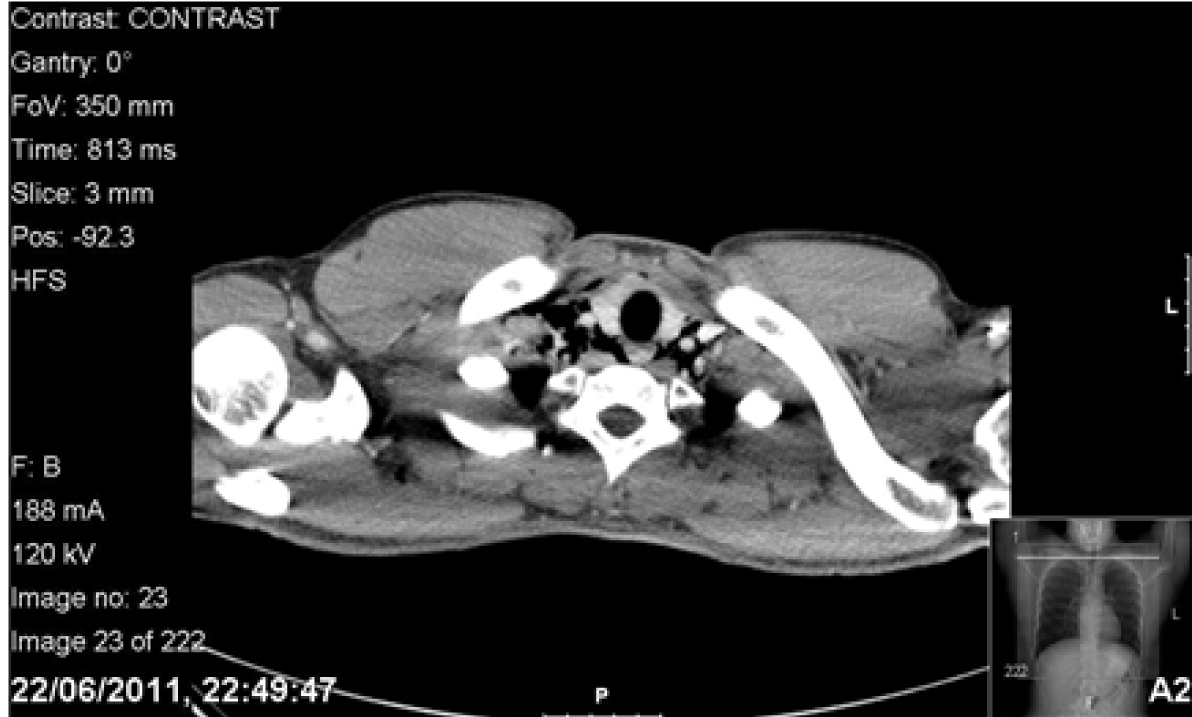

The patient returned home. However while taking his dinner, he experienced severe odynophagia describing the sensation like ‘swallowing glass’. The following day, his symptoms persisted so he consulted his surgical tutor whose registrar palpated the subcutaneous emphysema in his neck with no lymphadenopathy. An urgent X-ray of the neck revealed air in the subcutaneous tissues. Computed tomography (CT) scan of chest with contrast and Gastrografin swallow revealed a small leak outside the esophagus and pneumomediastinum. (Figure 1) Blood tests were unremarkable. The patient was transferred to a tertiary upper gastrointestinal centre with suspected Boerhaave’s syndrome. The tear was thought to be in the upper third of the esophagus. He was kept nil by mouth, supplemented with intravenous fluids and given prophylactic daily intravenous tazocin, metronidazole and fluconazole. Gastrografin swallow on the fifth day revealed no obvious leak, his symptoms had resolved. The patient was discharged with advice of a liquid diet for one week building to solids slowly thereafter.

Figure 1: Computed tomography scan of chest with Gastrografin contrast on initial admission illustrating a pneumomediastinum with leak of contrast into mediastinum.